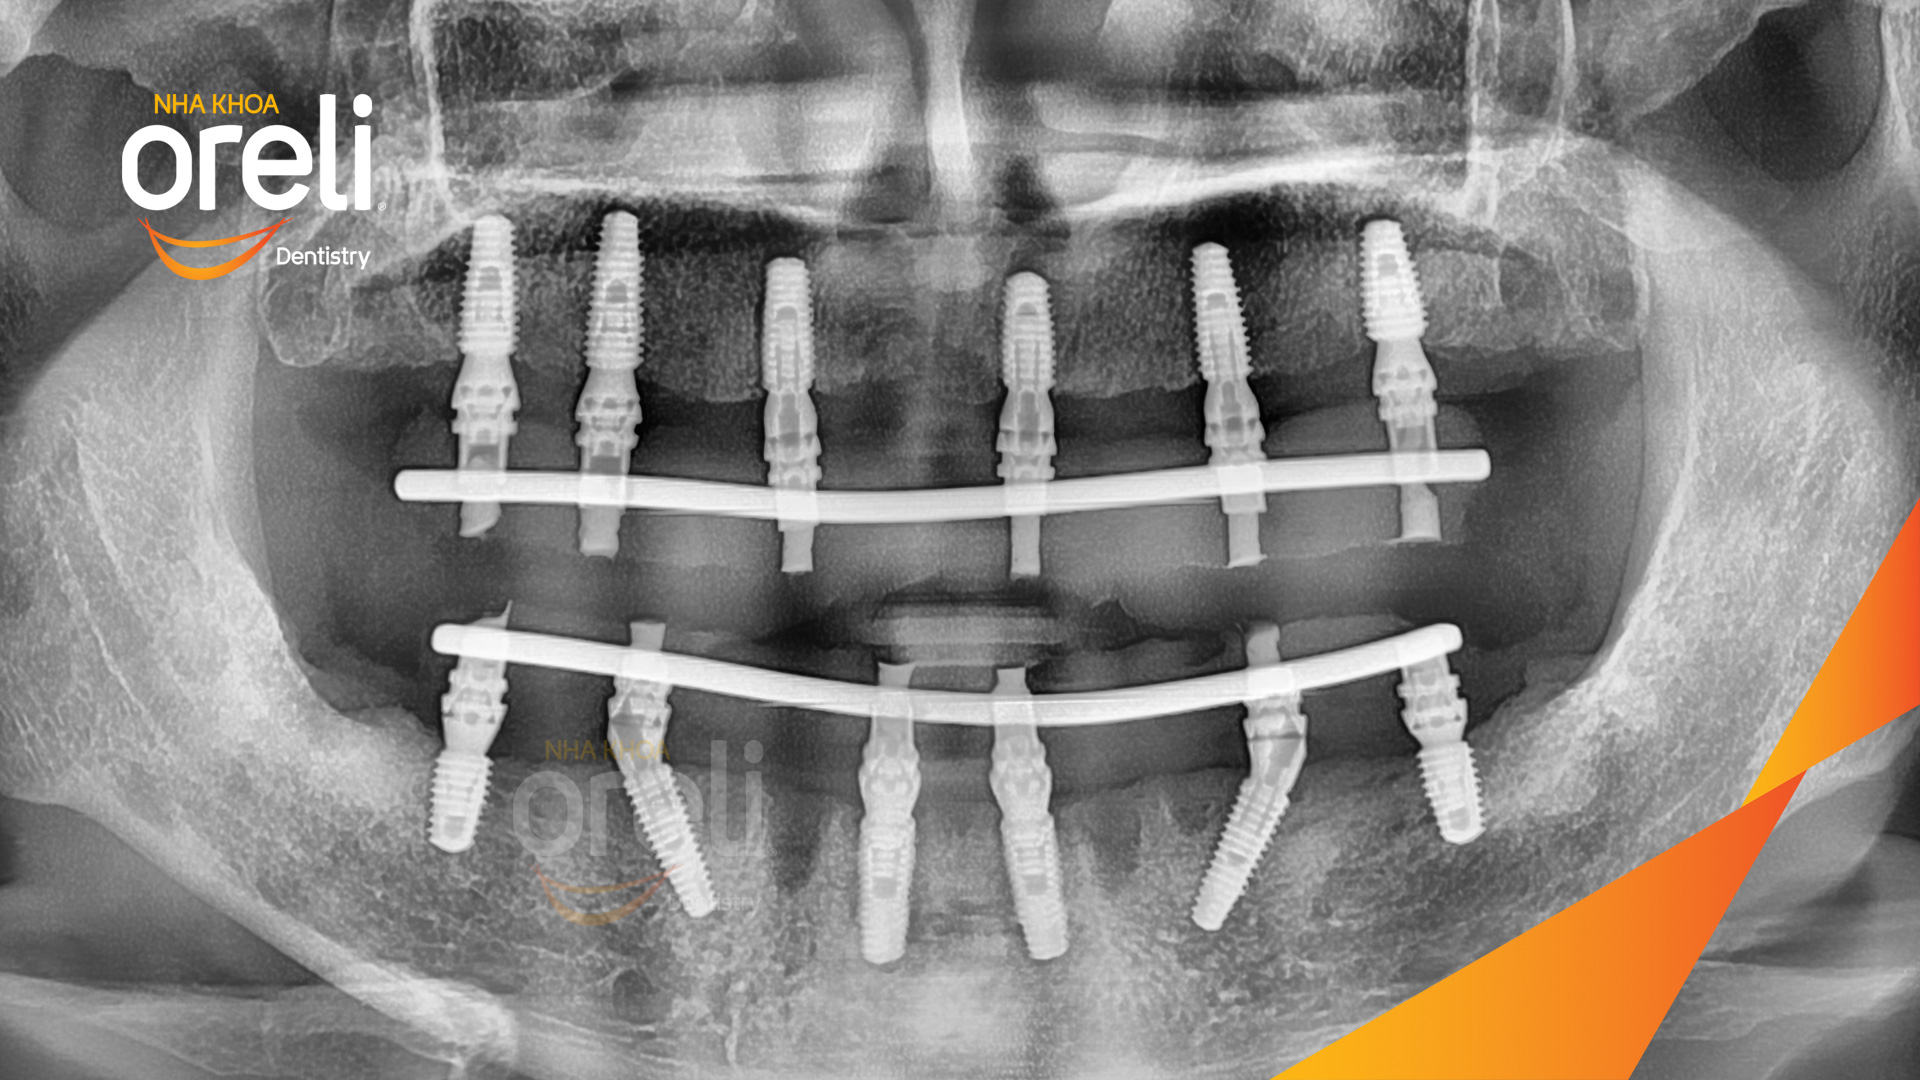

Tình trạng: Mất răng toàn bộ hàm trên và hàm dưới

Giải pháp: Trồng răng implant hai hàm với phục hình tạm

Hình ảnh thực tế